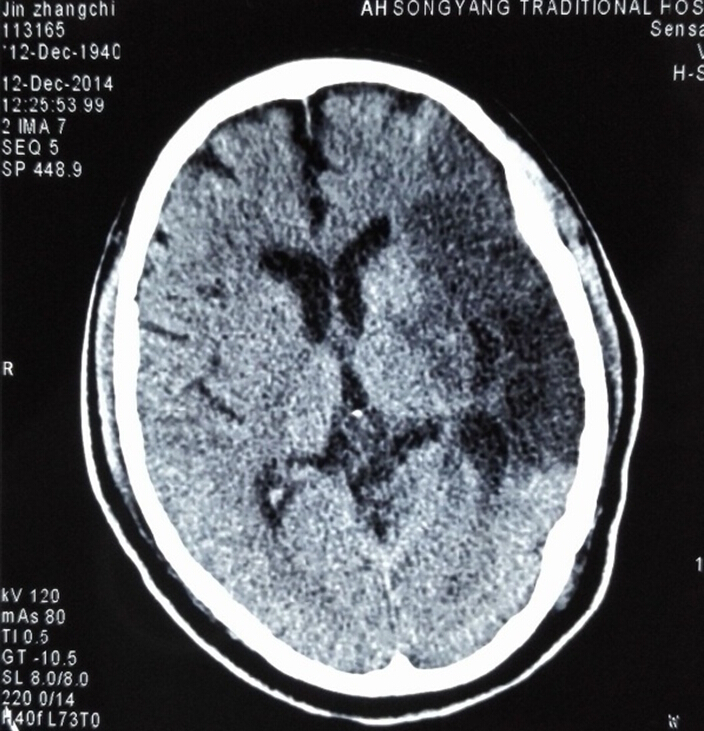

时间就是生命!在生死关头,我院派驻的专家王晓杭与家属作了必要而充分沟通并知情同意后,在相关科室密切配合下,带领该院医疗团队开始给患者进行溶栓治疗。后续病情发展让所有人都非常惊喜,当天下午金大伯右下肢就能抬了起来,第二天早上右上肢也能抬起来了。一天后复查的脑CT也证实了之前的判断,显示出左侧额、颞、顶叶大片新发脑梗死灶;如果不溶栓治疗的话肯定会导致严重的瘫痪。溶栓结束后,经过王晓杭医师和神经康复科医护人员的精心治疗,一周后金大伯虽然语言功能还没完全恢复,但已经可以独立行走(见图),日常生活也能基本自理。当他得知王晓杭就是他的主治医生后,他握着王晓杭的手久久不愿松开。

(附图为复查头颅CT显示左侧大面积脑梗塞及该患者与医务人员合影)